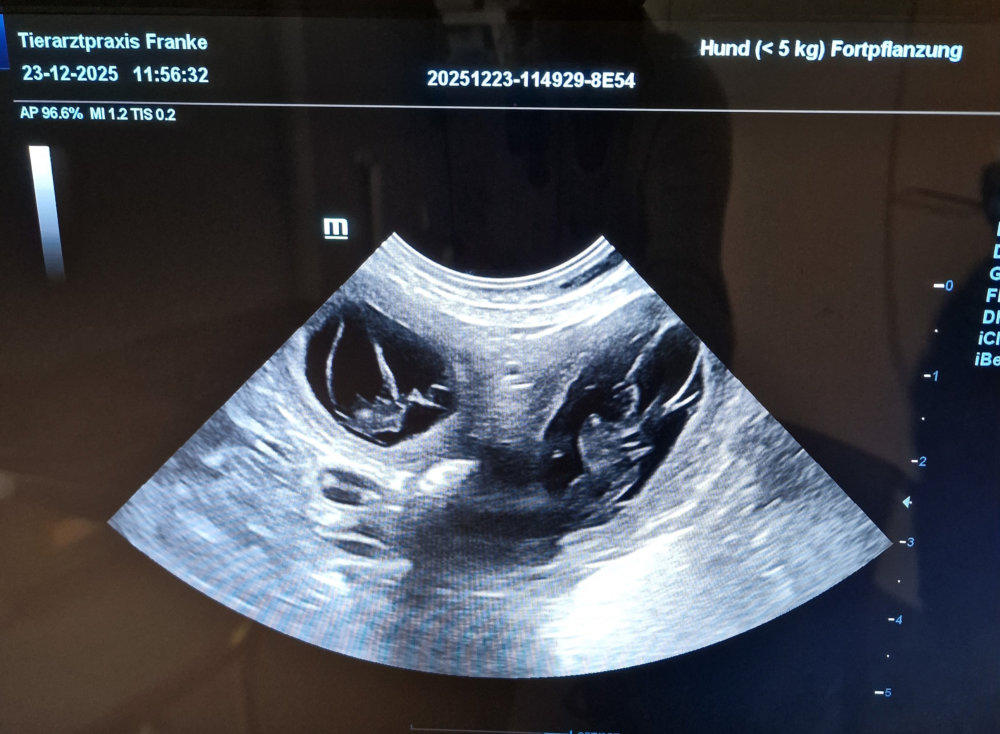

01.11.2025

Unser Frauli war mit Mala „Babys gucken“. Na, könnt ihr sie auch zählen? Smile. In ein paar Tagen ist es soweit. Freu. War nicht wirklich lange ruhig bei uns. Grins. Aber alles andere wäre ja auch langweilig. Hi, hi.